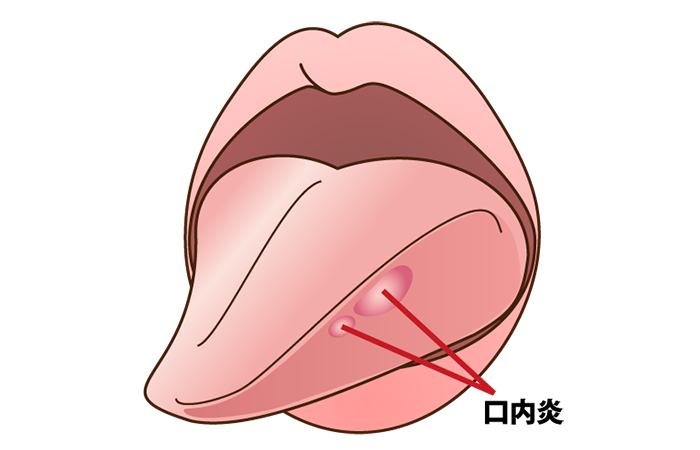

口内炎は、お口の中の粘膜にできるできものです。

頬や唇の裏、喉、舌などさまざまな場所にできて、痛みや不快感から日常生活にも支障をきたすこともあります。

口腔粘膜の疾患の一例

お口の中の粘膜に水疱・びらん・潰瘍・色素沈着などが見られる場合、次の疾患の可能性があります。

- アフタ性口内炎

- ウイルス性口内炎

- カタル性口内炎

- 口腔白板症

- 口腔扁平苔癬

- 天疱瘡

- 口腔カンジダ症

- 帯状疱疹

受診のタイミング

口内炎が2週間以上治らないときや、治ってもすぐに再発するときは、歯科口腔外科を受診しましょう。

症状が長引く場合は、がんなどの病気の可能性もあります。

こんな症状がありましたら、歯科口腔外科の受診をおすすめします。

- 痛みが強い

- 徐々に大きくなる

- 数が多い

- しこりがある